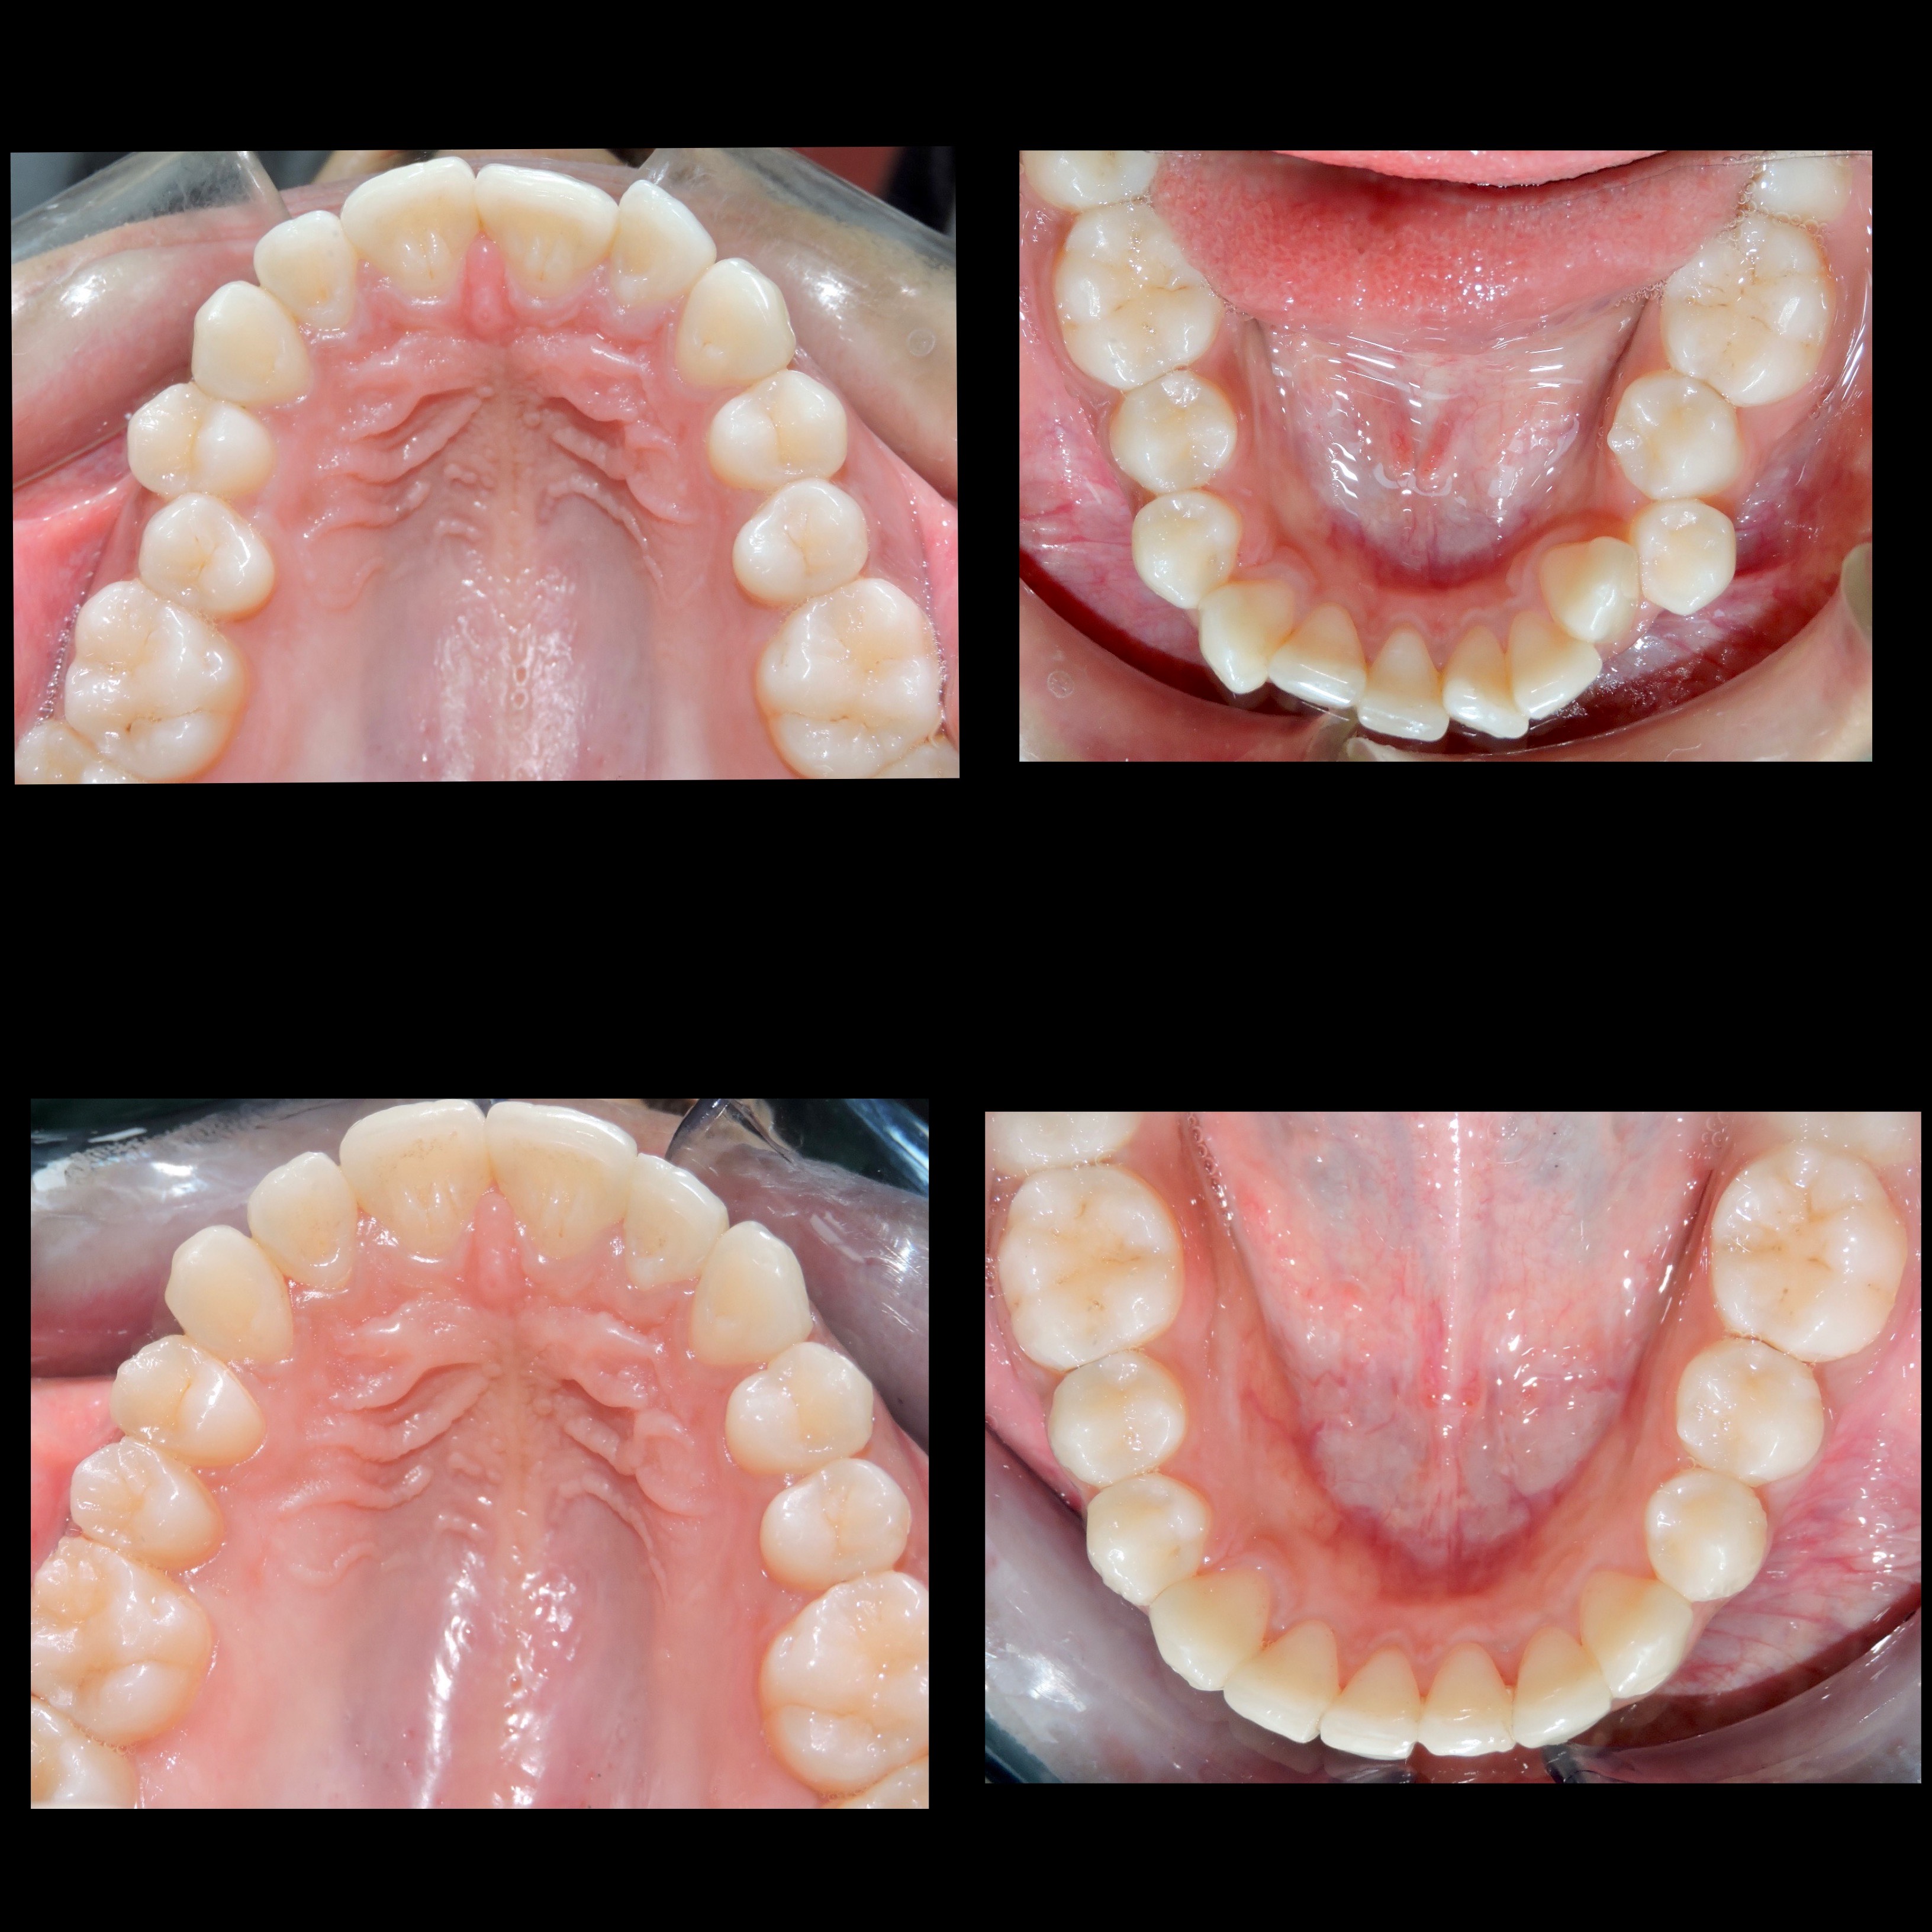

Gallery